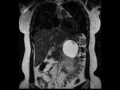

Mucinous cystic neoplasm (MCN)

MR images demonstrate a large T2 hyperintense cyst arising from the pancreatic tail. There is subtle internal mural nodularity which demonstrates no appreciable enhancement. These findings reflect a large mucinous cystic neoplasm, likely with internal old blood products